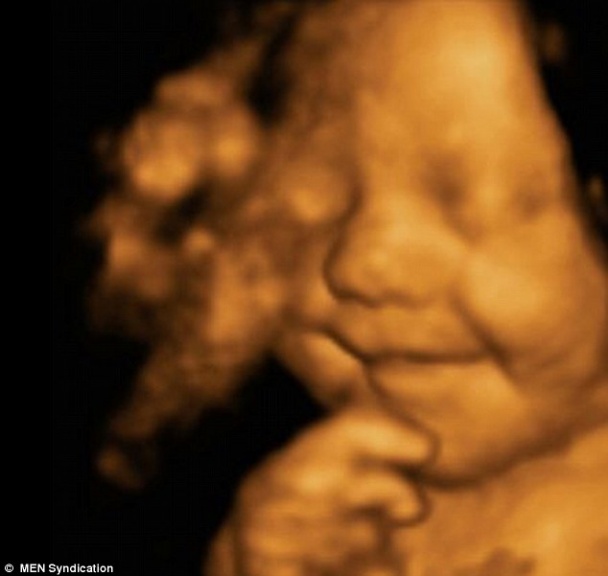

Мальчик не прекратил улыбаться и после своего рождения

Маленький Лео поразил всех окружающих своей улыбкой еще в утробе матери. Сейчас Лео исполнилось 5 месяцев, но он уже заслужено завоевал особую популярность благодаря своей очаровательной улыбке, сообщает ТСН.ua.Результаты УЗИ показали что малыш радовался этому миру, еще не родившись. На 31 неделе беременности, невероятная улыбка ещё не рождённого малыша зафиксирована на снимке. После своего появления на свет, мальчик продолжал улыбаться даже во время сна. Благодаря своей улыбке, пятимесячного Лео можно назвать самым счастливым ребёнком в Британии. Напомним, недавно благодаря Facebook девушка за 12 часов нашла родную мать. Уитни Брок опубликовала пост в Facebook с просьбой помочь ей найти свою родную биологическую мать и спустя всего 12 часов она ее отыскала. Читайте также: Агентство недвижимости быстро и качественно подбирает арендуемое жилье Радостно делать подарки близким и наблюдать как улучшается их настроение Организация и проведение корпоративных мероприятий | |